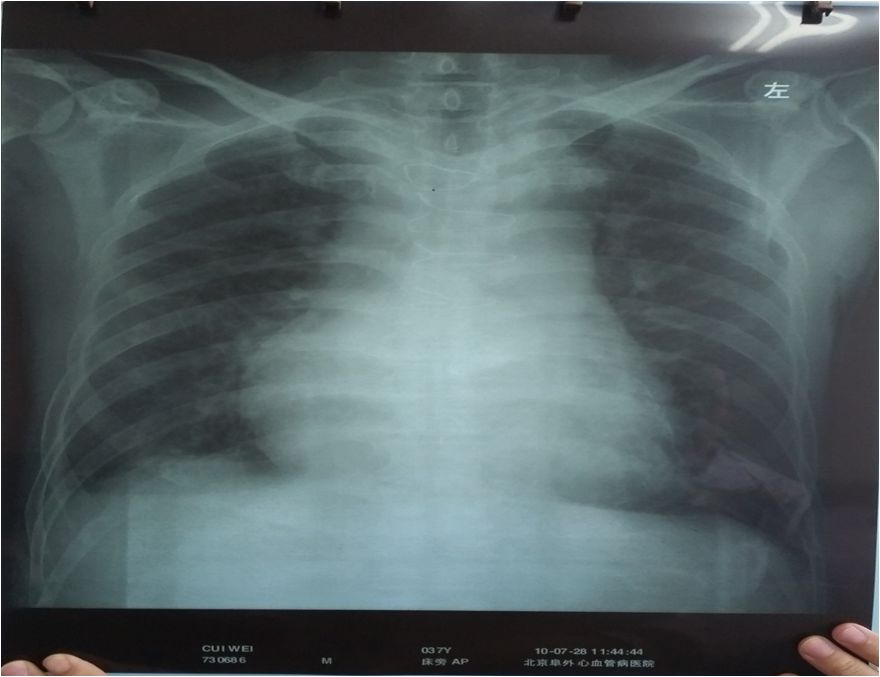

➤ 肺CT:双肺上叶及右肺中叶泡性肺气肿伴肺大泡,右侧胸腔积液,心包膜钙化。

心包钙化

肺动脉CTA示右肺动脉远端肺内分支较对侧略稀疏。主动脉瓣置换术后,心包不规则钙化,考虑缩窄性心包炎

心脏彩超:左心房53mm,右心房67*61mm,左室间隔增厚,右室壁增厚,右心室25mm,左室收缩功能正常低值。主动脉瓣机械瓣置换、功能正常,二尖瓣轻度狭窄并返流,三尖瓣中度返流,肺动脉高压(重度),估测肺动脉收缩压85mmHg,左室舒张明显受限,缩窄性心包炎不除外

近年结核发病率有抬头的趋势,在临床中缩窄性心包炎也要引起医生的重视。对于有明显体循环淤血体征而无显著心脏扩大时,应考虑缩窄性心包炎的可能。肺部CT显示心包周围钙化是缩窄性心包炎最重要的诊断依据。